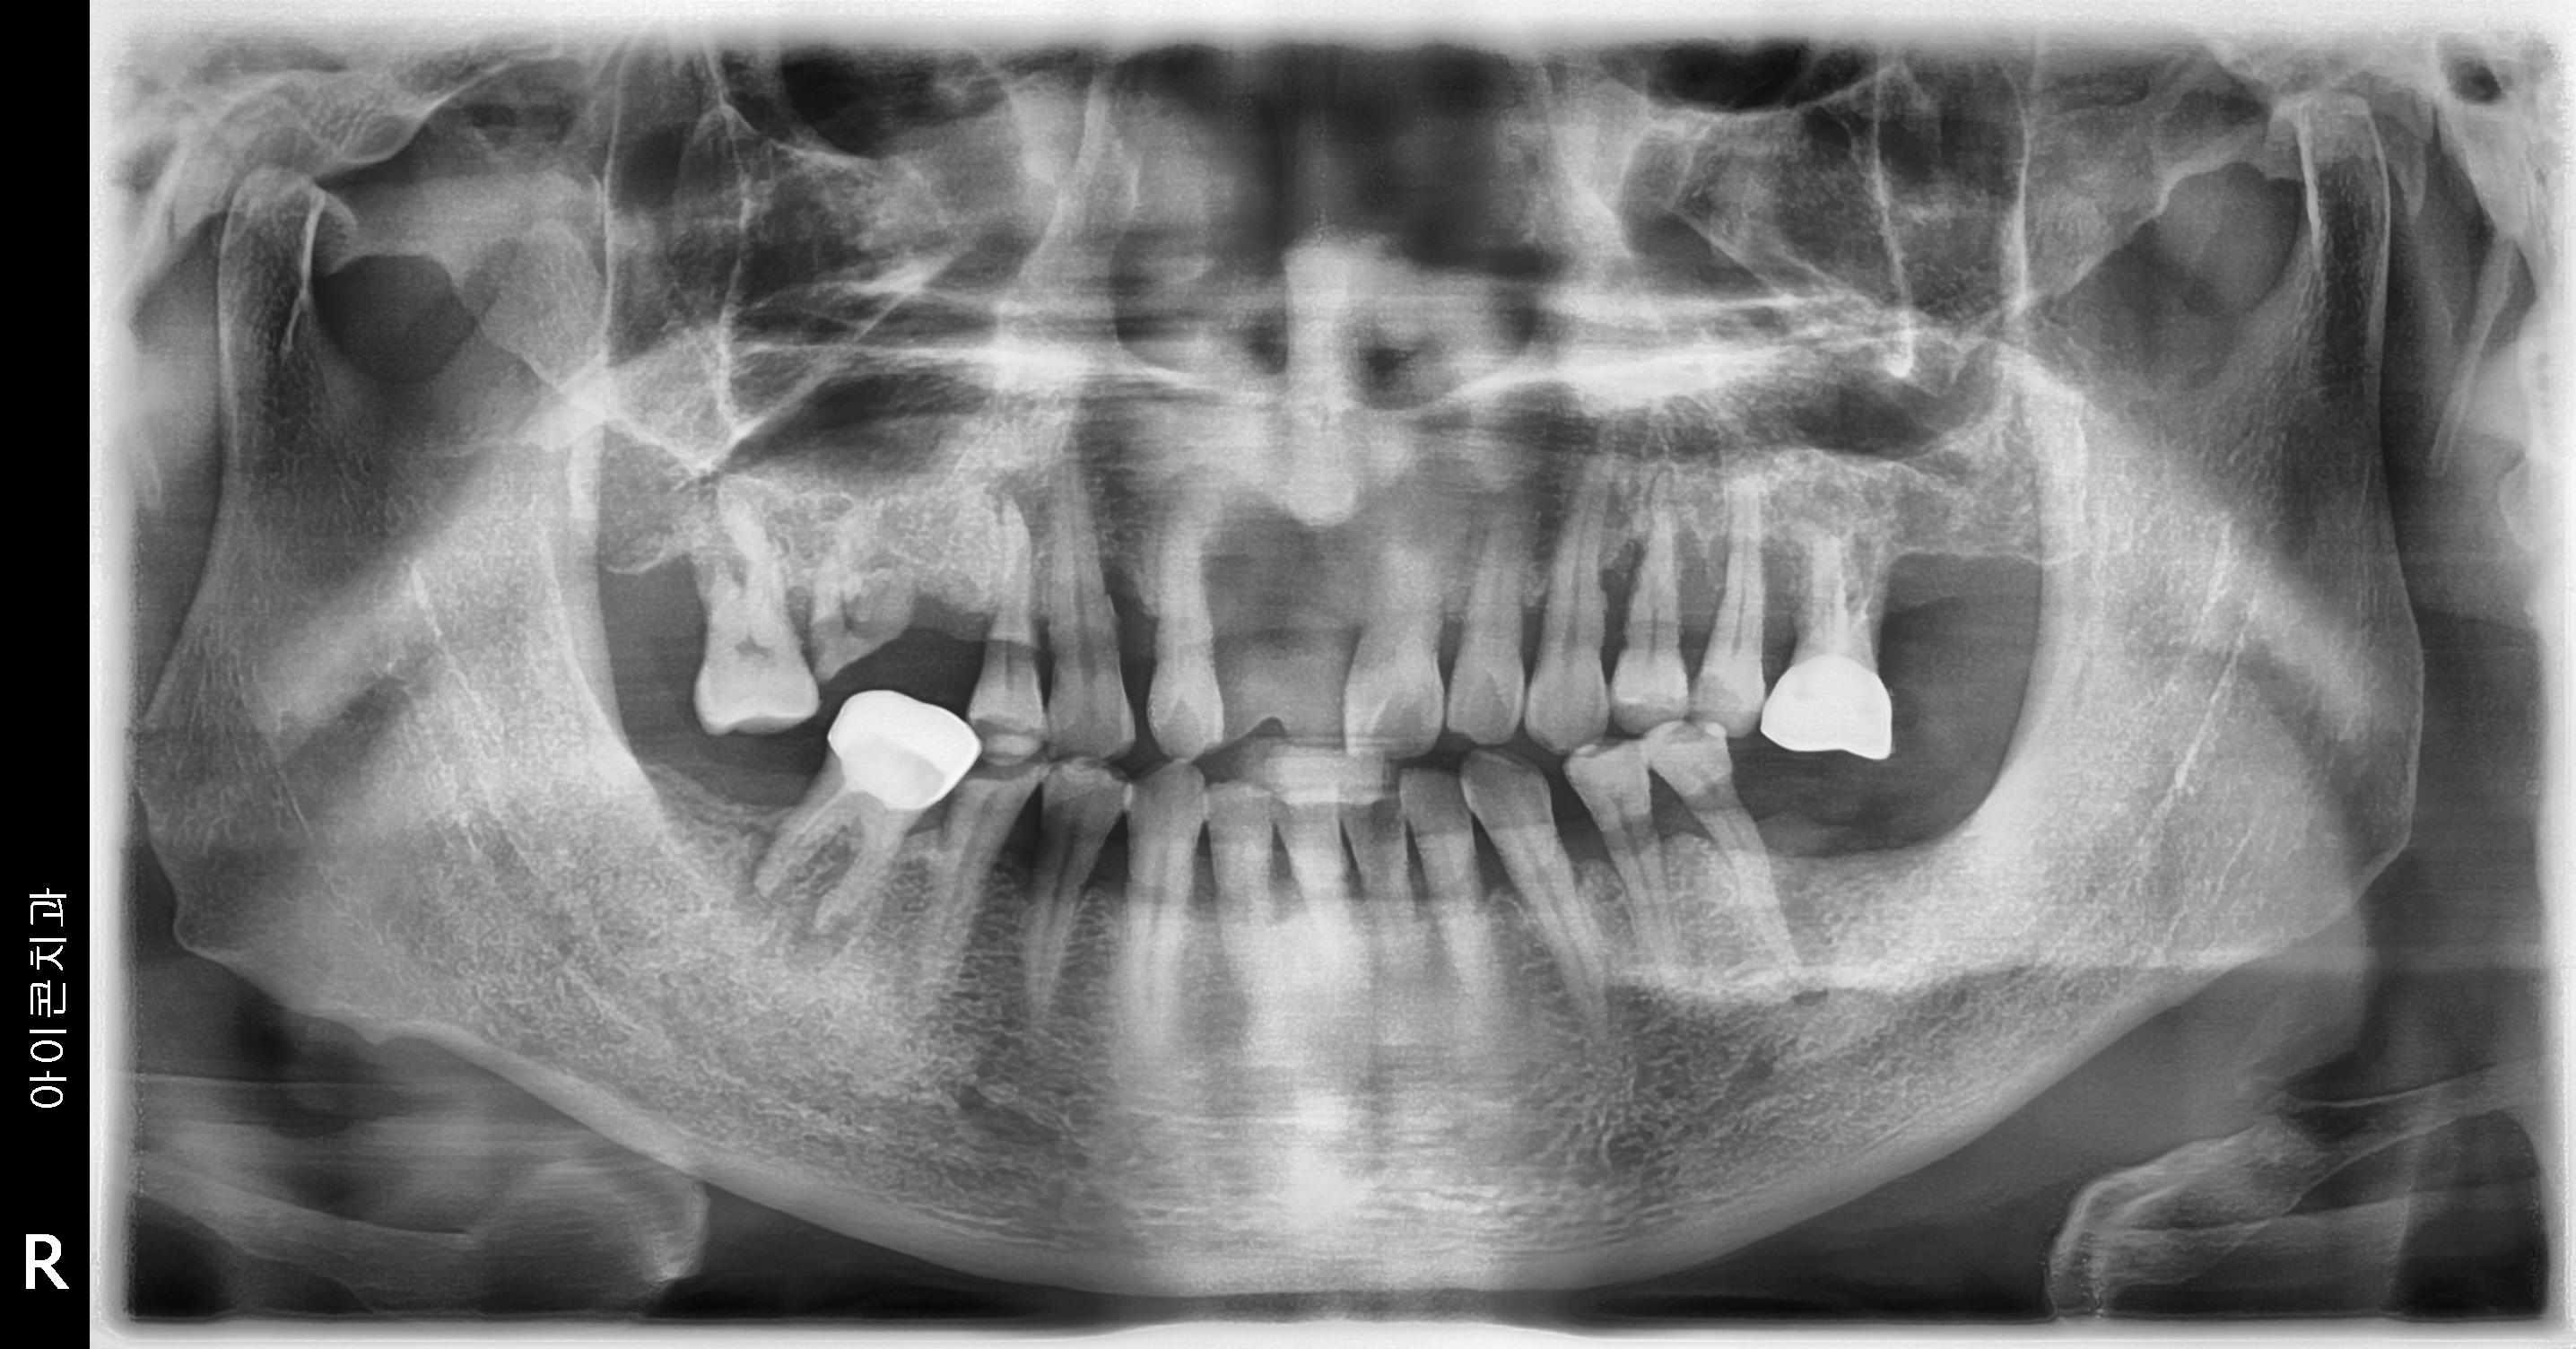

수술 전

수술 후

하악 임플란트 식립사례

전후사진